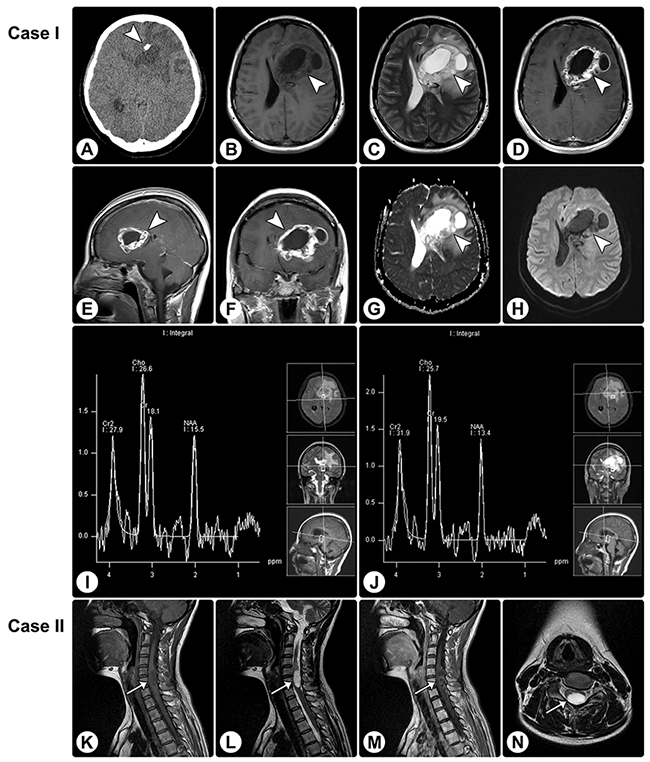

Figure 1: Rosette-forming glioneuronal tumor in the frontal lobe involving the lateral ventricle and rosette-forming glioneuronal tumor in the spinal cord. (A) CT reveals a hypodense lesion (arrowhead) in the right frontal lobe involving the lateral ventricle, and focal calcification is visible. (B and C) MRI shows a cystic-sold lesion (arrowheads) with hypointensity on axial T1WI (B) and hyperintensity on axial T2WI (C). (D–F) The axial (D), sagittal (E), and coronal (F) contrast T1WI show heterogeneously remarkable enhancement in the solid portion of the tumor. (G and H) The apparent diffusion coefficient (ADC) map (G) and DWI (H) show facilitated diffusion. (I and J) MRS demonstrates an elevated choline value, reduced NAA value, and absence of lactate or lipid peaks. (K–M) MRI of another patient reveals an intramedullary mass (arrows) in the spinal cord, with hypointensity on sagittal T1WI (K), hyperintensity on sagittal (L) and axial (N) T2WI, and heterogeneous enhancement on sagittal contrasted T1WI (M).

Figure 2: Rosette-forming glioneuronal tumor in the pineal region involving the tectum. (A) CT reveals a slight hypodense lesion (arrowhead) in the pineal region involving the tectum, without calcification. (B and C) MRI shows a cystic-sold lesion (arrowheads) with hypointensity on axial T1WI (B) and hyperintensity on axial T2WI (C). (D–F) Axial (D), sagittal (E), and coronal (F) contrast T1WI show no significant enhancement. (G and H) The ADC map (G) and DWI (H) show facilitated diffusion. (I and J) MRS demonstrates an elevated choline value, reduced NAA value, and absence of lactate or lipid peaks.